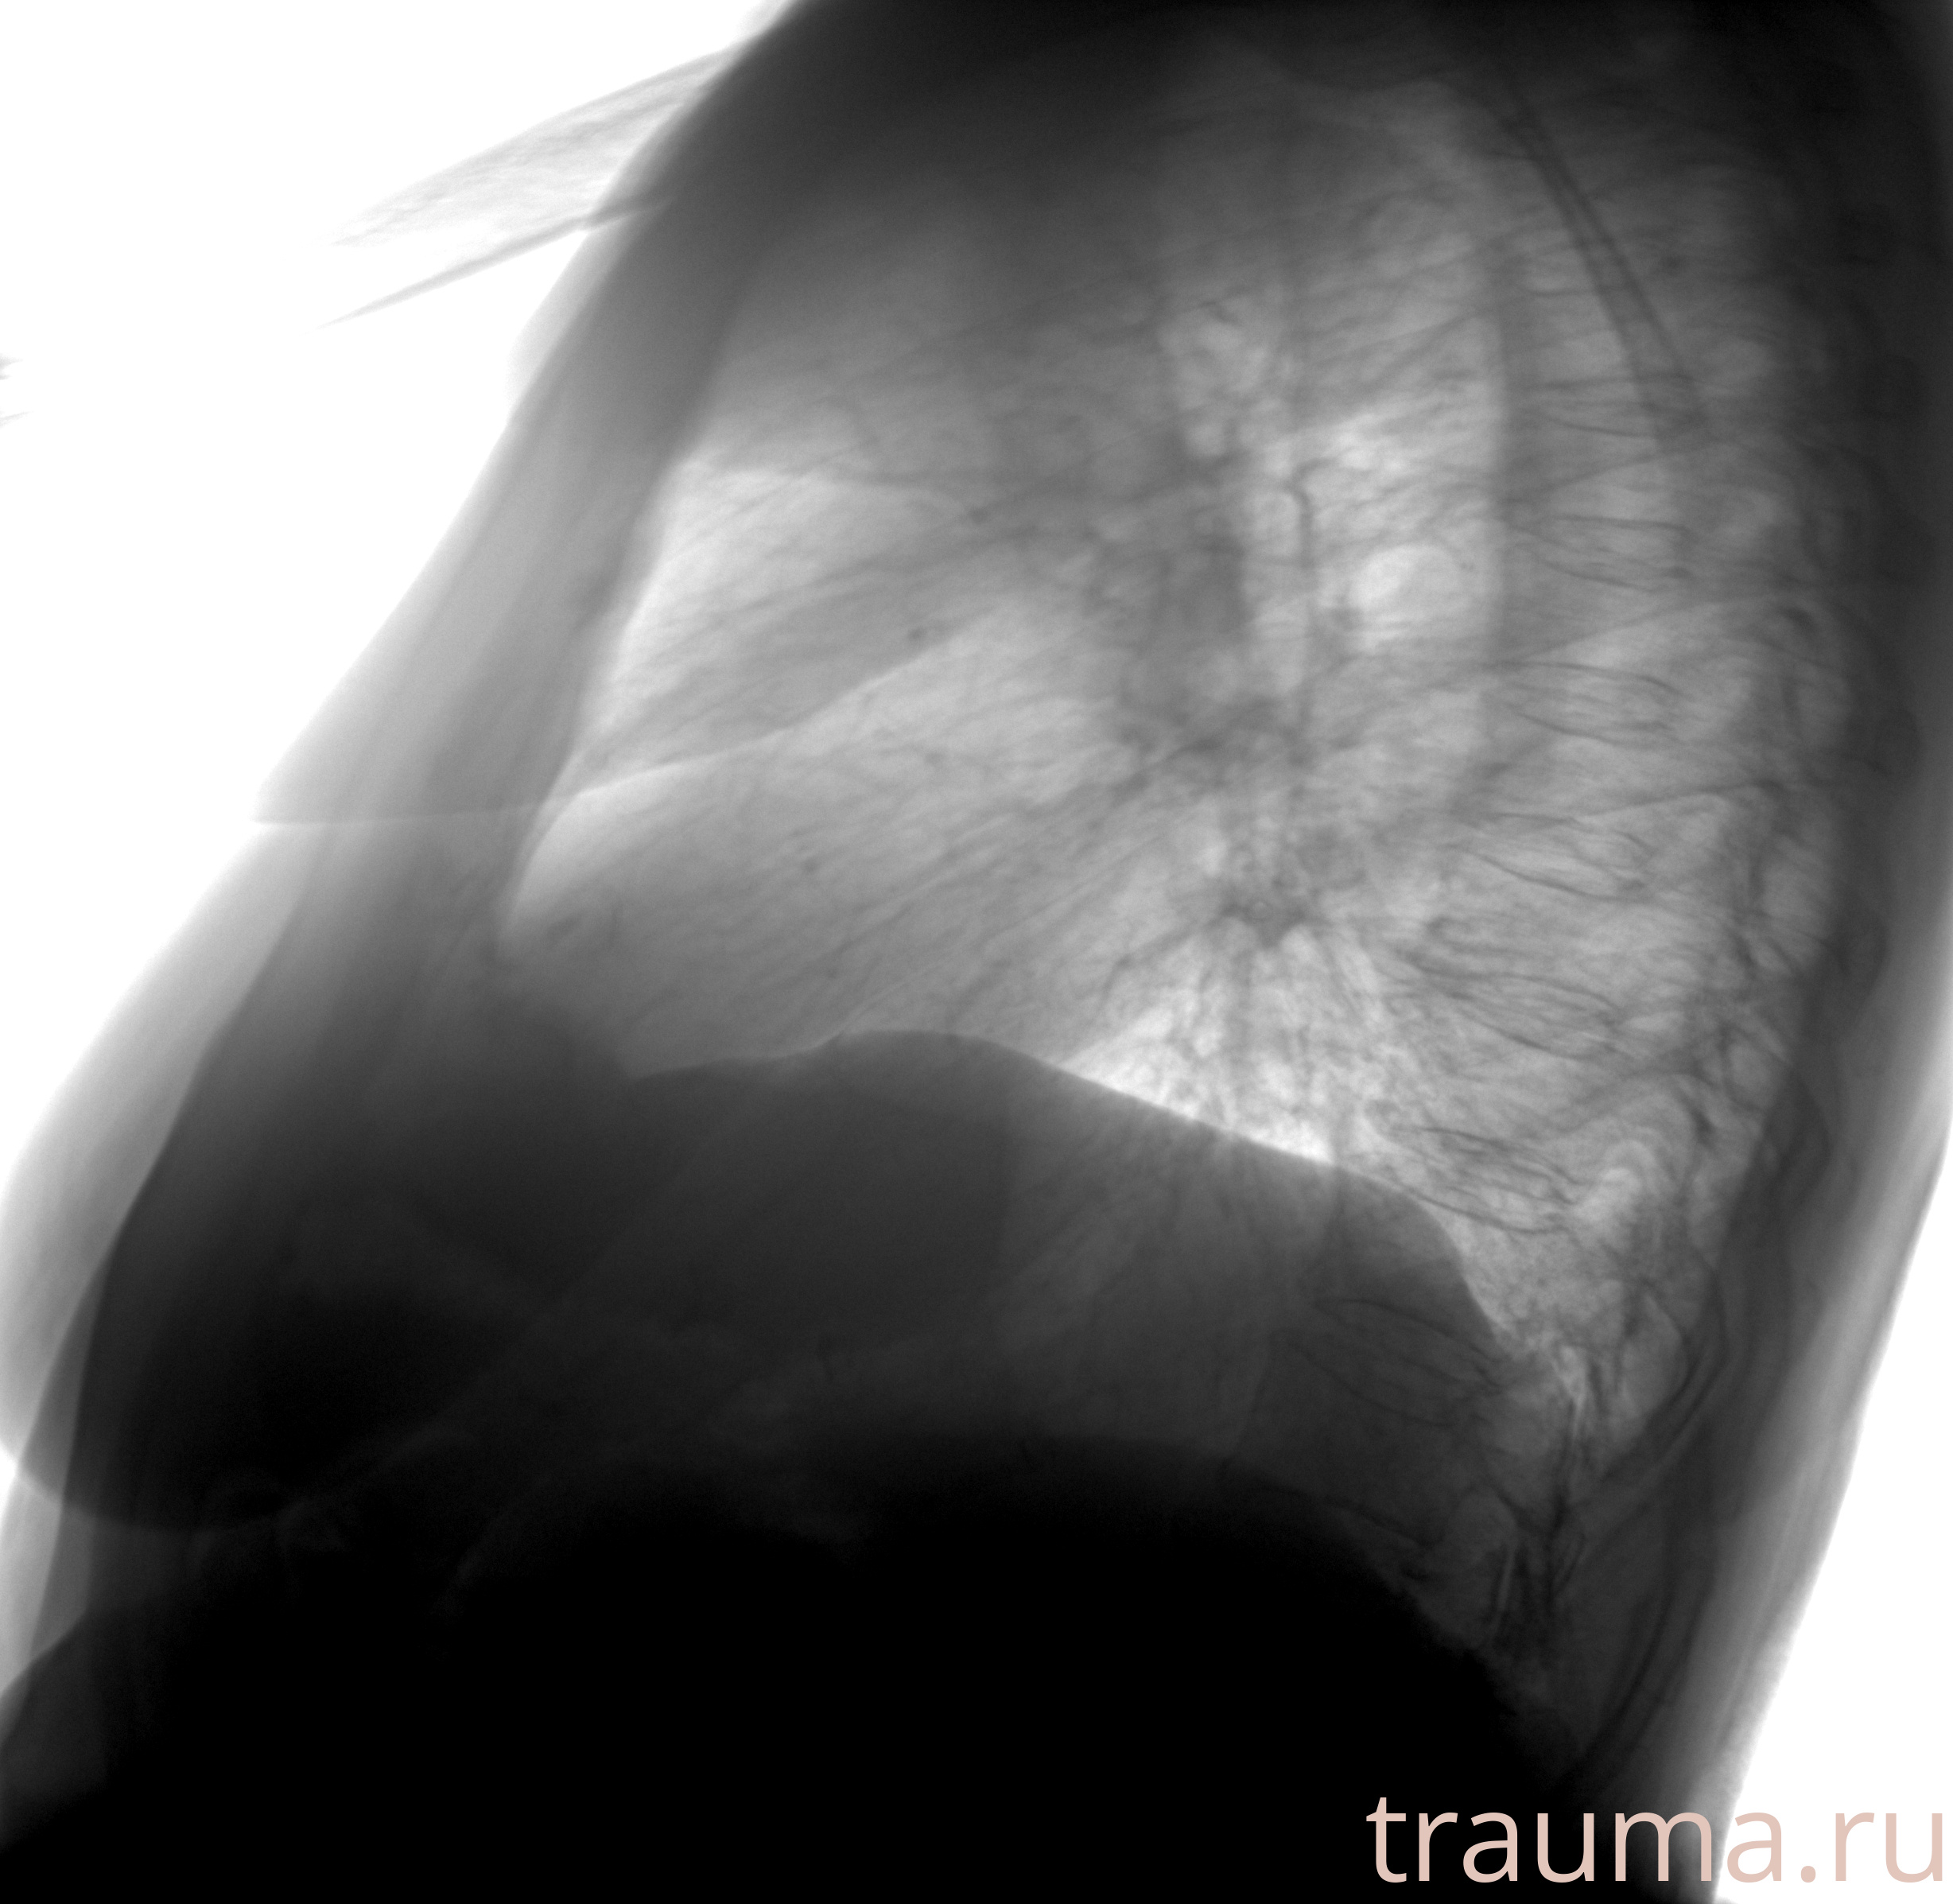

Рентген на дому: по вашему адресу приезжает врач-рентгенолог, травматолог-ортопед с мобильным рентгеновским аппаратом, проводит диагностику травмы или заболевания, делает необходимые рентгенограммы, дает рекомендации по дальнейшему лечению. Получить качественные снимки в домашних условиях возможно благодаря уникальной методике, разработанной МосРентген Центром для института  Склифосовского